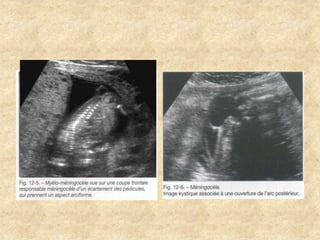

Pathologie des parties molles

Pathologie du système nerveux central

Malformations fœtales d’expression précoce Pathologiedes parties molles Pathologie du système nerveux central Pathologie des parois Pathologie urinaire Pathologie des membres Pathologie cardiaque